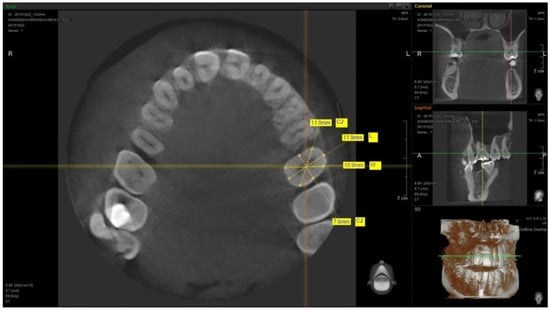

| L | C1 | H | C2 | L | C1 | H | C2 | L | C1 | H | C2 | L | C1 | H | C2 | L | C1 | H | C2 | |

| Arithemic Average | 6.633 | 6.302 | 5.889 | 6.787 | 6.085 | 5.65 | 4.447 | 5.533 | 7.693 | 7.023 | 5.358 | 6.536 | 8.509 | 7.611 | 4.569 | 6.957 | 10.320 | 9.963 | 7.577 | 10.084 |

| Standard Deviation | 0.546 | 0.478 | 0.600 | 0.538 | 0.525 | 0.545 | 0.579 | 0.506 | 0.578 | 0.599 | 0.532 | 0.679 | 0.619 | 0.634 | 0.602 | 0.704 | 0.751 | 1.023 | 0.696 | 1.159 |

| Median | 6.6 | 6.2 | 5.9 | 6.8 | 6.1 | 5.7 | 4.4 | 5.45 | 7.7 | 7 | 5.4 | 6.45 | 8.45 | 7.8 | 4.55 | 7 | 10.35 | 10.1 | 7.6 | 10.3 |

| Minimum Value | 5.8 | 5.5 | 4.5 | 5.5 | 5.1 | 4.4 | 3.4 | 4.5 | 6.4 | 5.9 | 4.5 | 5.2 | 7.2 | 6.2 | 3.1 | 5 | 8.1 | 7.3 | 6.4 | 7.1 |

| Maximum Value | 8 | 7.5 | 7.7 | 8.6 | 7.4 | 7 | 6.4 | 6.9 | 8.9 | 8.6 | 6.6 | 8.2 | 9.8 | 8.7 | 5.8 | 8.3 | 11.8 | 11.9 | 9 | 12.4 |